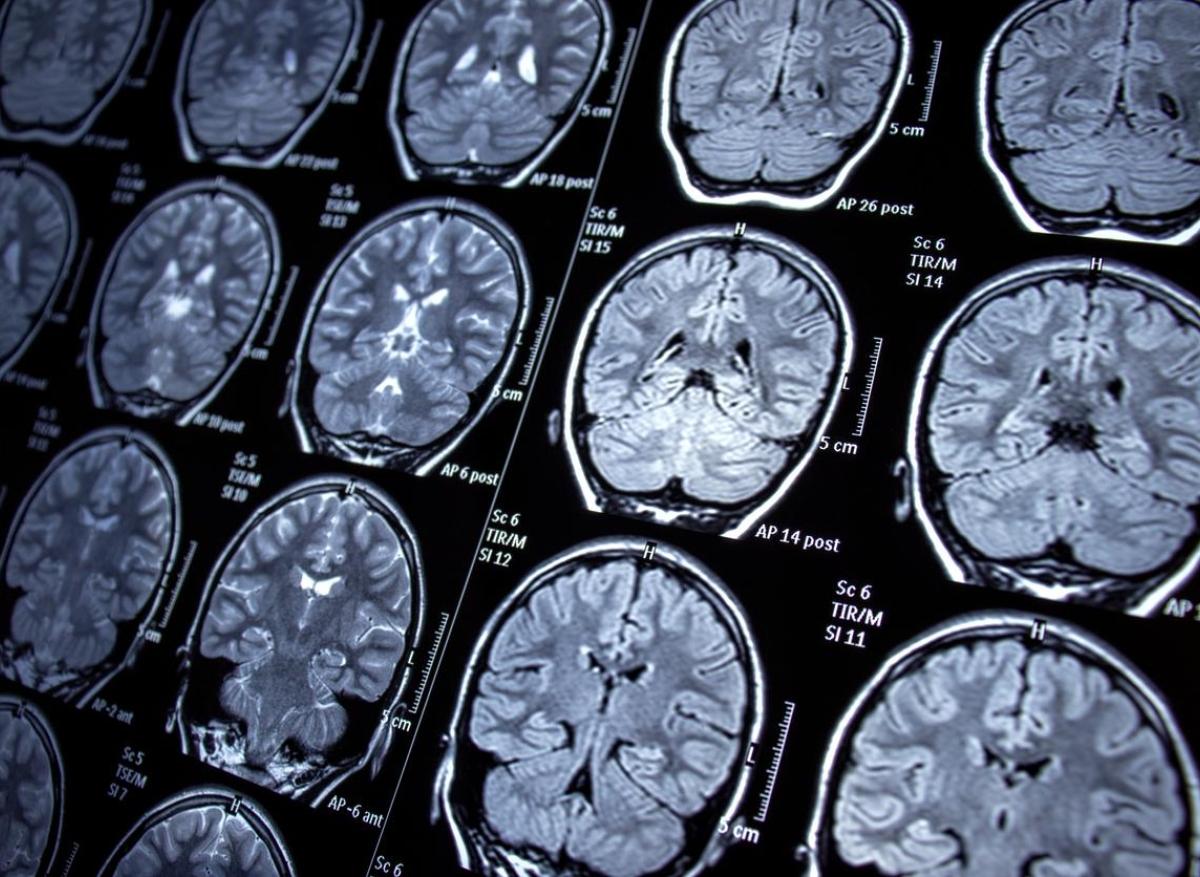

Une découverte majeure dans la recherche sur la maladie d’Alzheimer vient d’éclairer le rôle crucial des cellules immunitaires cérébrales dans cette pathologie dévastatrice. Des scientifiques ont démontré que les microglies présentes dans les cerveaux de personnes atteintes d’Alzheimer présentent des comportements distincts par rapport à celles des individus sains, ouvrant potentiellement la voie à de nouvelles approches thérapeutiques.

L’analyse, menée sur des tissus cérébraux humains, révèle que ces cellules protectrices adoptent plus fréquemment un état pré-inflammatoire, compromettant leur capacité défensive naturelle.